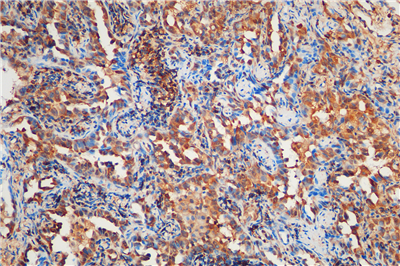

免疫组化是应用免疫学基本原理——抗原抗体反应,即抗原与抗体特异性结合的原理,通过化学反应使标记抗体的显色剂(荧光素、酶、金属离子、同位素) 显色来确定组织细胞内抗原(多肽和蛋白质),对其进行定位、定性及定量的研究,称为免疫组织化学技术(immunohistochemistry)或免疫细胞化学技术(immunocytochemistry)。

免疫组化的分类: 免疫组织化学技术按照标记物的种类可分为免疫荧光法、免疫酶法、免疫铁蛋白法、免疫金法等。

服务内容:包含抗体,包埋,切片,染色以及拍照。(每个样本提供一张照片包含阳性面积)加拍另外计费。